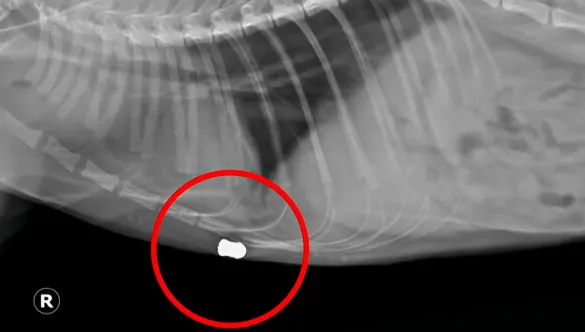

"Още при първия преглед преглеждащият лекар установи, че има входна рана и директно каза, че за нея това е простреляна с въздушна пушка", обяснява друга жителка пред Нова. Рентгеновите снимки потвърждават съмненията, като ясно показват сачми, заседнали в телата на котките.